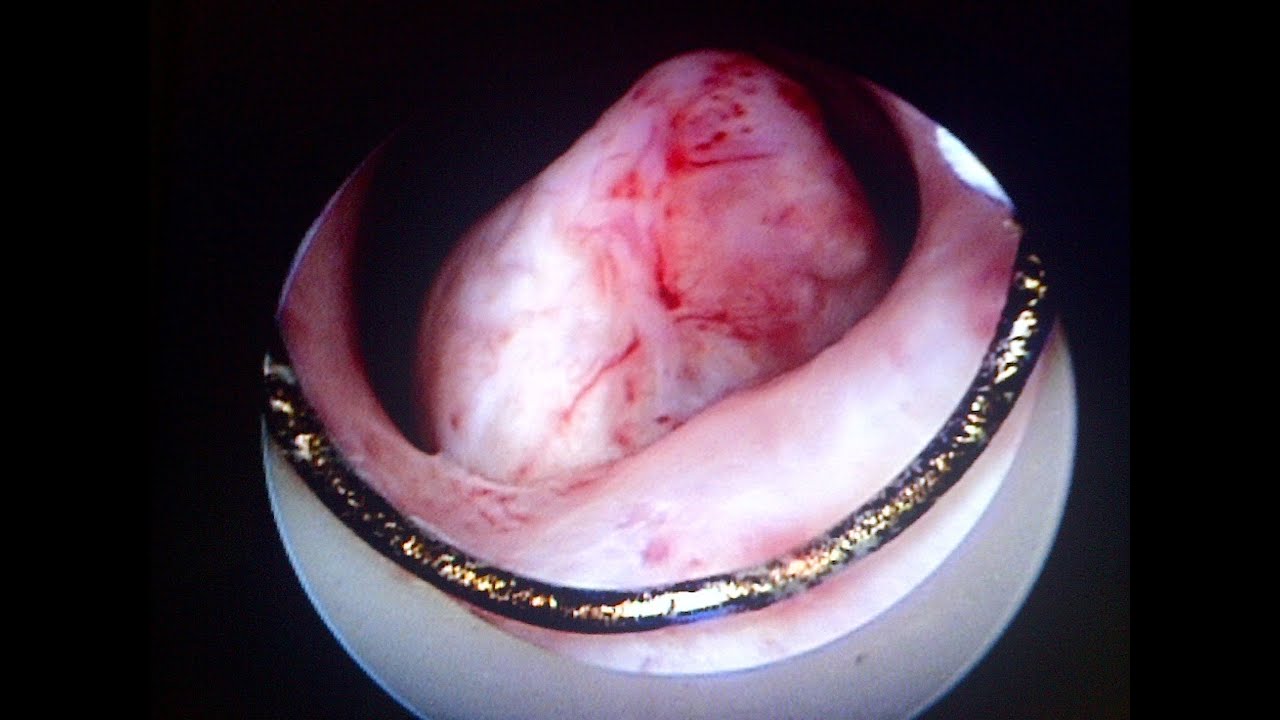

WebOvulación después de la histeroscopia Casos de éxito en el embarazo tras una laparoscopia Rachel Gurevich es una defensora de la fertilidad, autora y galardonada. WebDespués de la histeroscopia, no debe planificar un embarazo de inmediato. Experiencia de mujeres sometidas a histeroscopia Muchas mujeres que se han. WebForo sobre el embarazo exitoso después de una histeroscopia. La duración media de los procedimientos fue de 28±17 minutos y el tamaño medio de los miomas fue de.

Source: Youtube.com